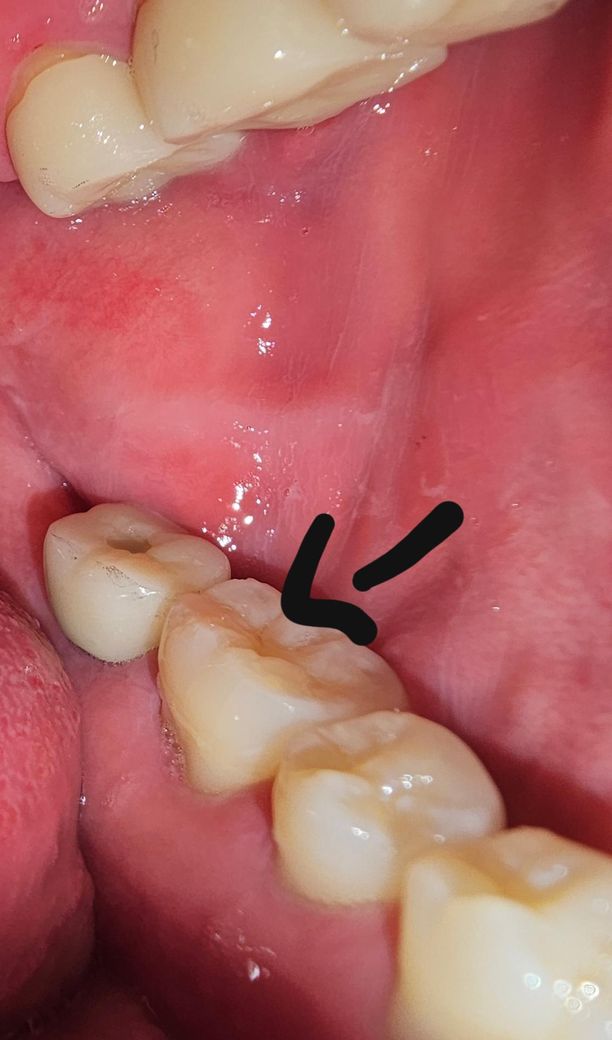

평소에 워터픽 > 치실 > 양치 > 30~60분 후 가글 하는 편인데 저 어금니 잇몸이 좀 내려가 있어서 걱정입니다 ㅠㅠ 어떻게 해야 될까요 많이 심각한가요?

잇몸퇴축도 있고 어금니 마모도 있네요 평소 딱딱한 음식섭취가 많다면 줄이고, 이갈이나 이악물기 증상 있으면 치료 받으세요

잇몸퇴축은 저 상태정도로는 잇몸이식까진 필요없습니다